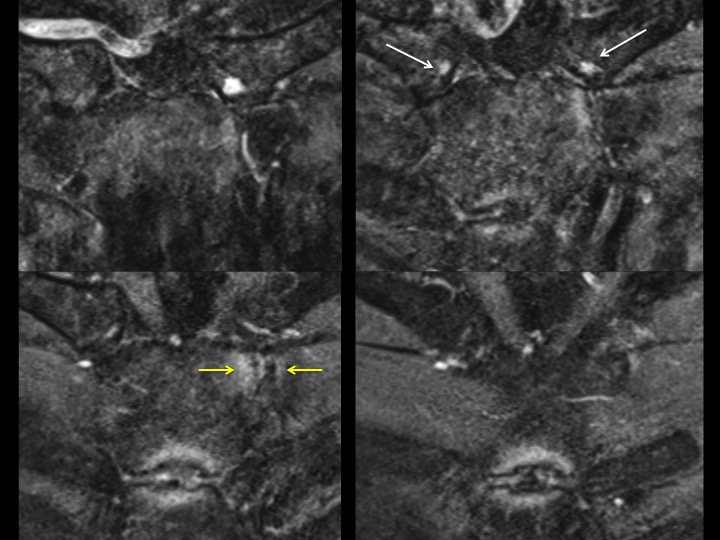

The referrer ordered MRI of each clavicle, but the left side included the manubrium and upper sternum as well at the medial right clavicle. Symptoms are only near the left sternoclavicular joint. There are bilateral bright foci in the articular cartilage of the medial clavicle (white arrows), with subtle subchondral erosion but no BME on the left. There is left sided subchondral edema at the costomanubrial junction (yellow arrows). Obvious erosion with edema at the manubriosternal articulation The referrer did not notice any rash, though it sounds like he didnt think to look. Im thinking SAPHO and seronegative spondyloarthropathies; agree or not? The orthopedist says he will refer him to rheumatologist and will get me follow up when available. Reference article.